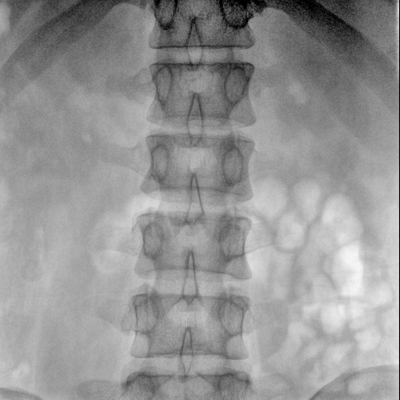

骨科: 經皮錐體成形術、經皮椎間盤臭氧治療術、胸脊椎固定、骨活檢、腰椎內固定術等。

優質平板探測器、可靈活升降調節SID、獨特圖像處理系統、高品質濾線柵,大視野成像清晰不失真。